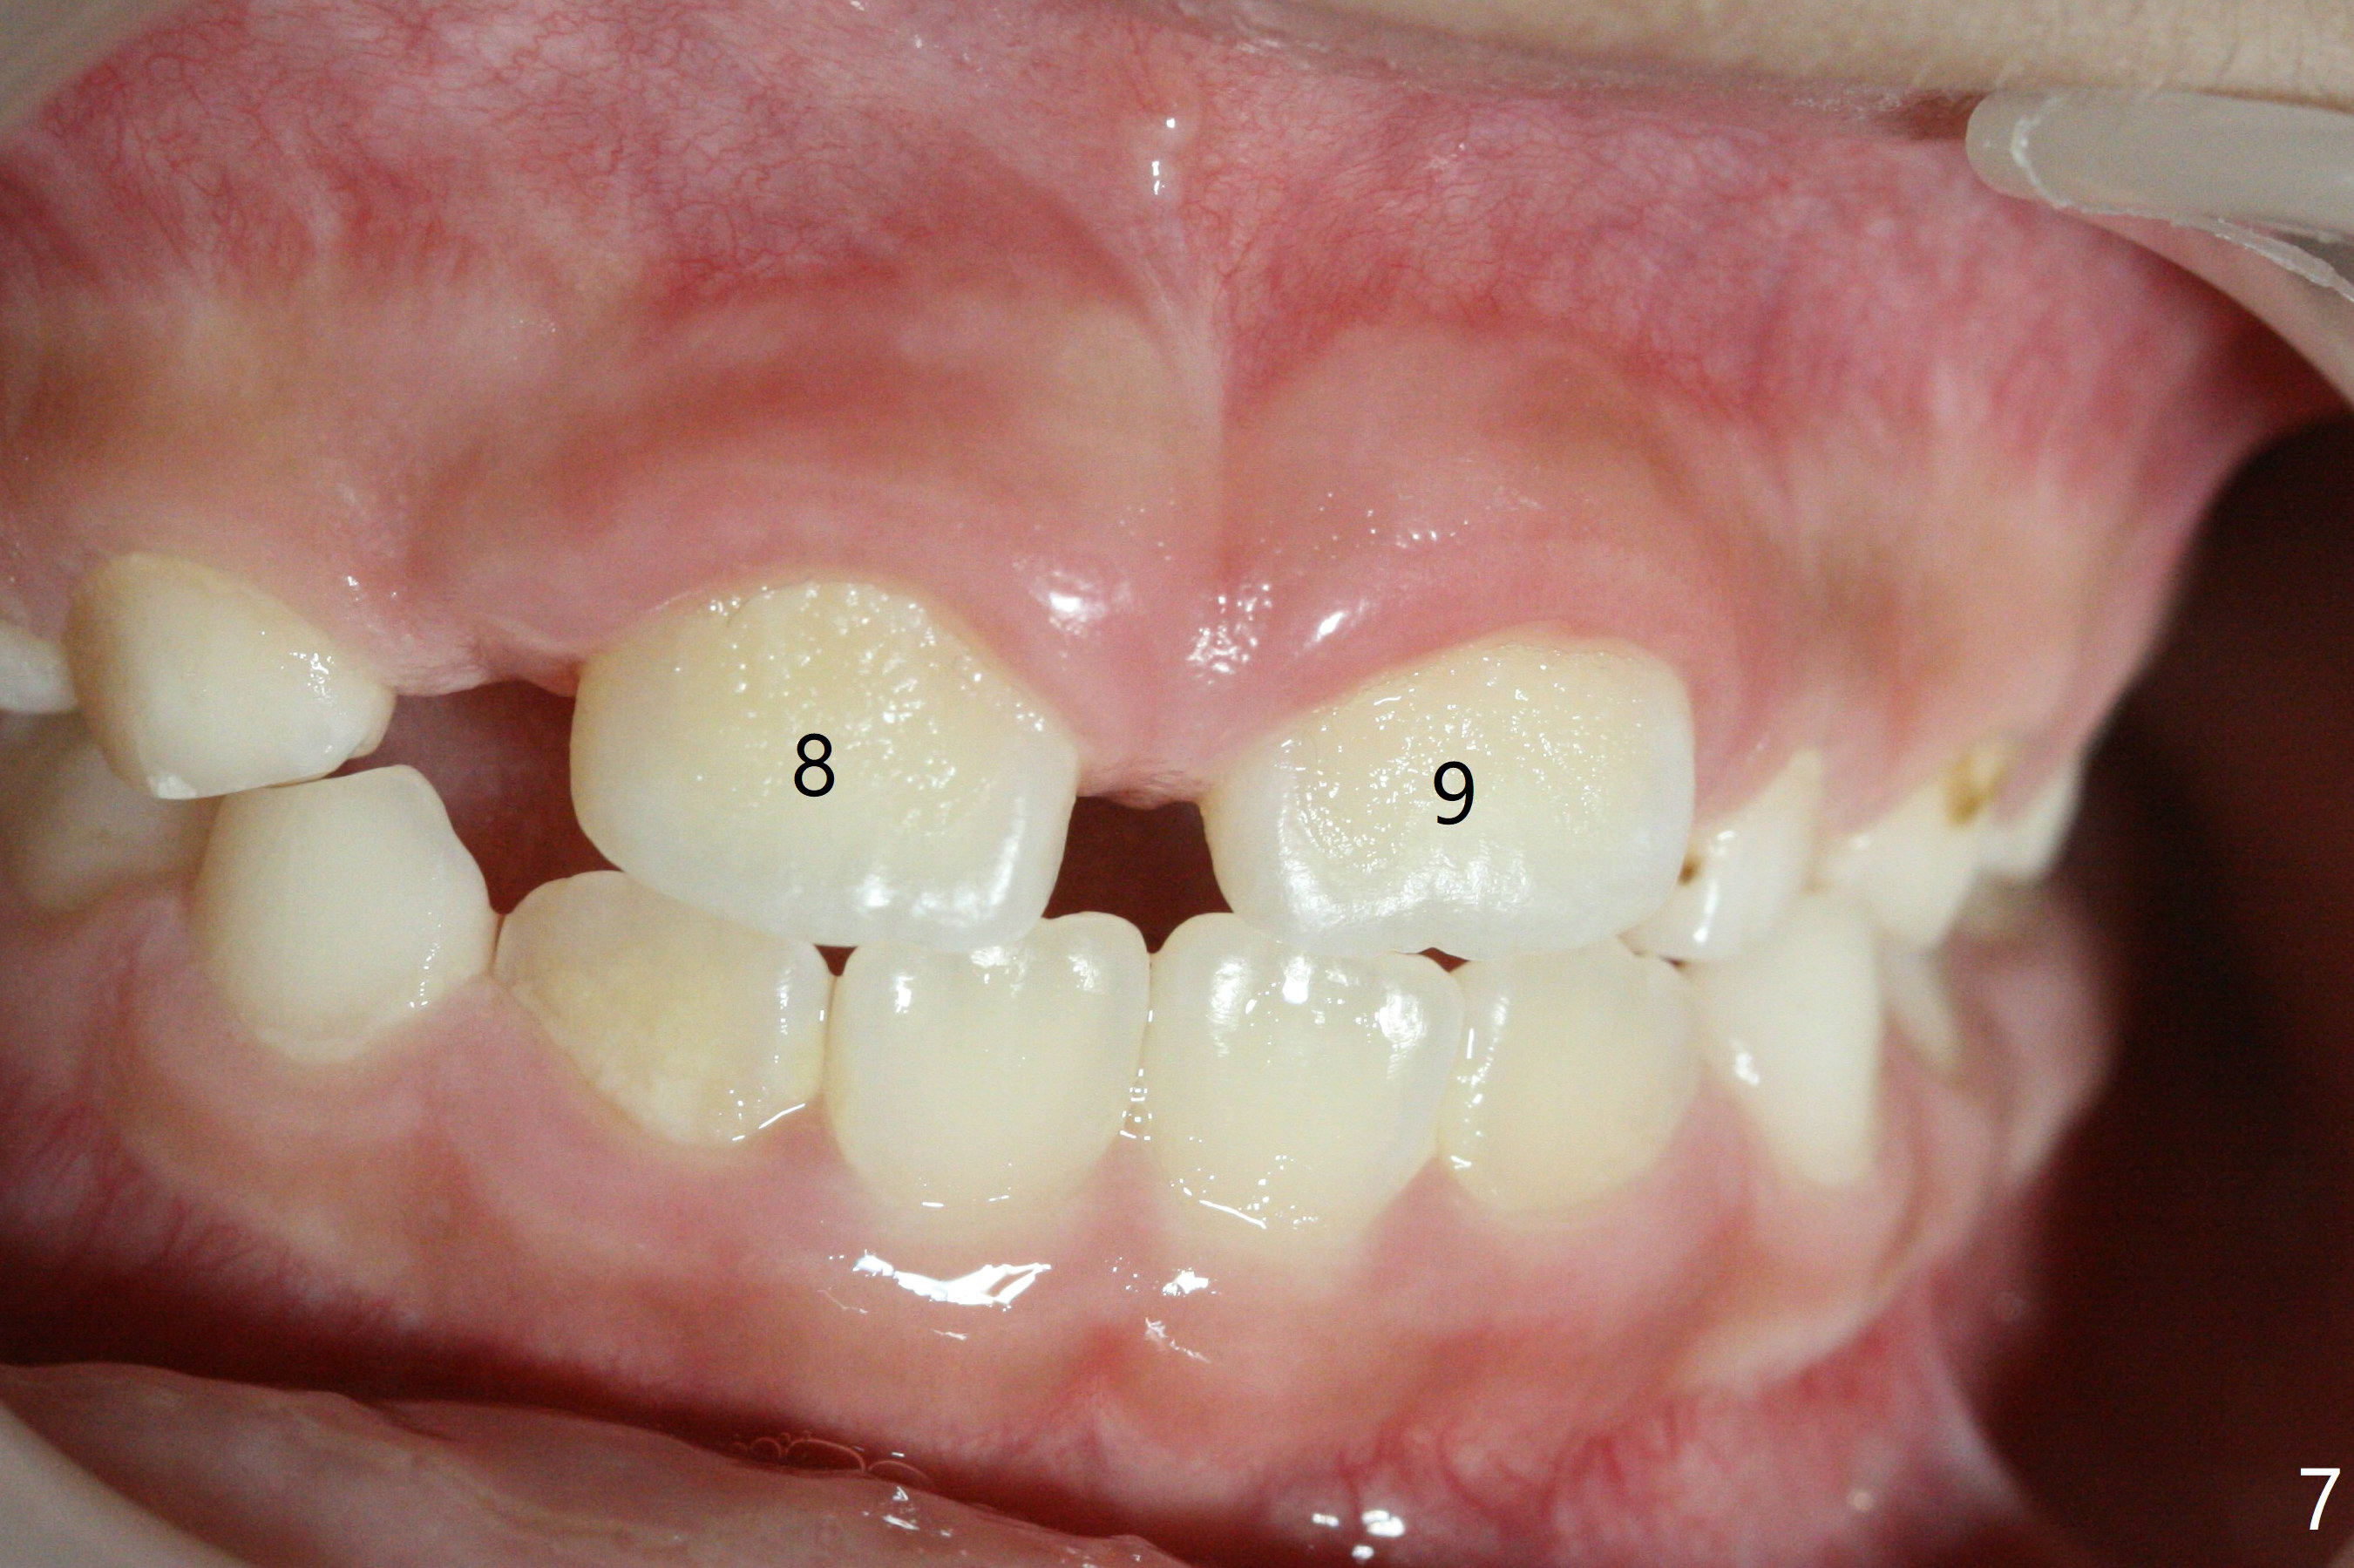

There is a large diastema between the upper central incisors (Fig.7). The left anterior palate is slightly elevated (Fig.8 *). In fact the cortex overlying the mesiodens (Fig. 9 *, 11 <) is to be removed with a surgical handpiece in order to extract the mesiodens (Fig.10). The left central shifts mesial in 7.5 months postop, whereas the right one remains in place (Fig.12). The tooth #7 is unerupted 1 year 4 months postop (Fig.13).